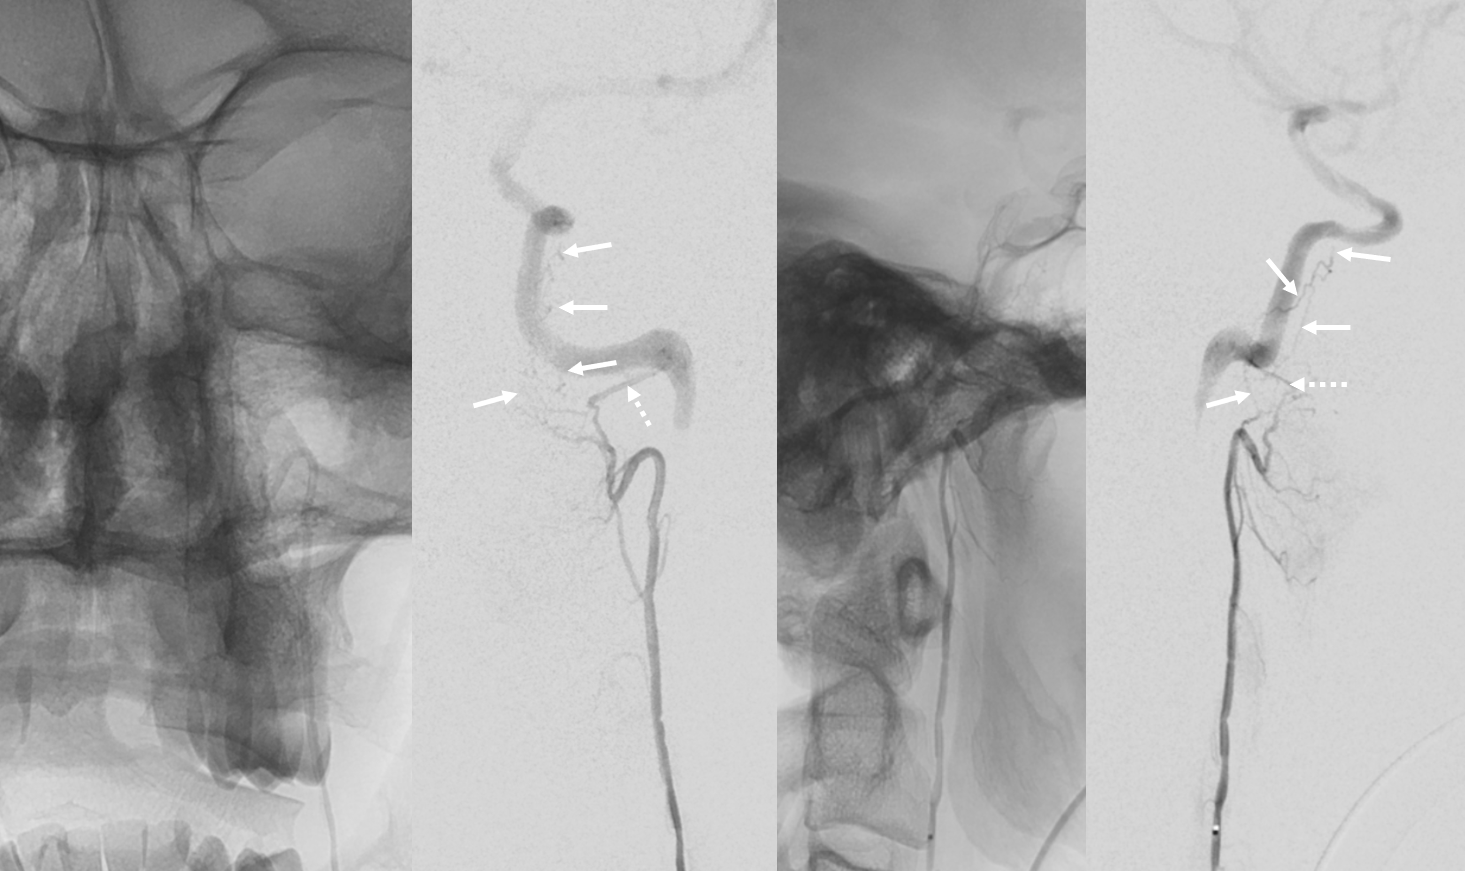

AP and lateral bone and native mask injections of the AP artery in a patient with high-grade vertebral artery stenosis at C3 level. The descending branch of the hypoglossal divison exiting FM and running along the posterior aspect of C1 and C2 is well seen on the lateral projections. In the AP, it is off-midline, sending branches to its contralateral homolog (not visible)

AP view of right Hypoglossal division microcatheter injection, with exquisite demonstration of the odontoid arcade. A descending branch of the right hypoglossal division opacifies the arcade with visualization of the contralateral AP anastomosis and vertebral arteries. The arcade is seen to advantage because the remainder of right hypoglossal division has been embolized, thereby diverting flow into the arcade.